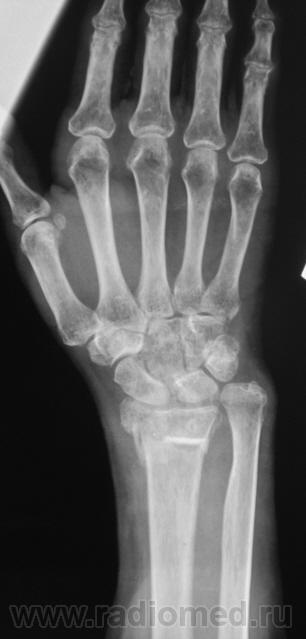

Пусть интересуется... Гипс снят рановато, стояние отломков - неудовлетворительно,хотя бывает и хуже

Если срок сращения 4 недели, то признаки консолидации выражены соответственно сроку достаточно хорошо. Перелом компрессионный, поэтому произошел вывих в л/л суставе. Можно или нет его было устранить в амбулаторных условиях - судить не берусь. Осколок кортикала в луче "захряснет", может, рассосется - ничего страшного.

неприятная ситуация(особенно если не было первичной репозиции) есть оппределенные правила ведения таких переломов, первичный снимок, сразу после репозиции, через 4-5 дней после репозиции и если нет вторичного смещения в гипсе то через 4-5 недель уже без гипса. ситуация на данный момент спорная, лучше наложить аппарат Илизарова для дальнейшей иммобилизации и профилактики контрактуры л\зап сустава. если возраст пациентки почтенный, то гипсовая иммобилизация доолжна быть продлена до 8 недель.